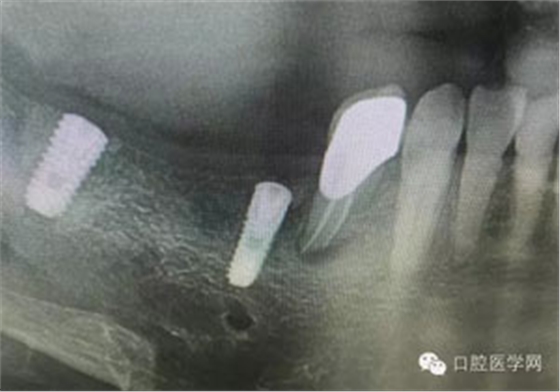

病例1:患者迫切希望保留自己的這一顆牙齒,根尖周陰影比較大,二度松動(dòng).而且旁邊有種植修復(fù)體,和患者溝通好后,治療好后觀察一個(gè)月后冠修復(fù),因?yàn)橛蟹N植的后期修復(fù),所以有了機(jī)會(huì)觀察,術(shù)后三個(gè)月和術(shù)后四個(gè)月,根尖恢復(fù)的還算不錯(cuò),希望能夠繼續(xù)觀察下去.這樣子的病例,做的時(shí)候我們一定要非常的小心,和患者要有充分的溝通以及不同科室的溝通然后決定怎么樣做比較好,假如就是出現(xiàn)了問題,到時(shí)候我們也比較好處理些,免得我們自己到時(shí)候不好收?qǐng)觥?/span> 病例2:364647中齲的樹脂充填,現(xiàn)在樹脂的充填材料非常之多,有些時(shí)候,我們感覺有了好的材料我們就可以做出好的修復(fù),可是這是在我們有扎實(shí)的基本功的基礎(chǔ)上的,我們可以沒有那么好的樹脂,那么多的顏色選擇,修復(fù)的那么的逼真,但是我們至少要恢復(fù)患者牙齒的功能,將腐質(zhì)去除干凈,薄壁弱尖消除掉,選擇好適應(yīng)癥,給患者以盡可能好的修復(fù)。 來源于KQ88